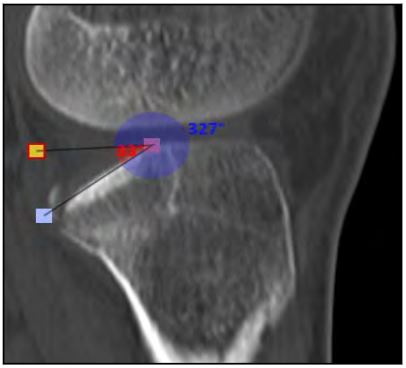

Fueron calculados el porcentaje del área de superficie articular comprometida (PASAC) del cuadrante posterolateral, (cálculo entre el área articular del platillo tibial lateral sano y lesionado); el tipo de depresión (TP) y la profundidad (PF) (distancia entre la superficie articular normal y la superficie más deprimida) o el ángulo de declinación (AD) (ángulo resultante entre una línea trazada en la superficie articular normal y otra línea en la superficie articular inclinada).

En la Tabla 2 se exponen las mediciones tomográficas de los pacientes estudiados, donde se obtuvo en promedio un PASAC 35 % (rango 20- 47 %) (Fig. 6), PF 2.50 mm (rango 1.7-3.8) y AD 29.5° (rango 24-35°) (Fig. 7).

Figura 7. AD: ángulo de declinación.